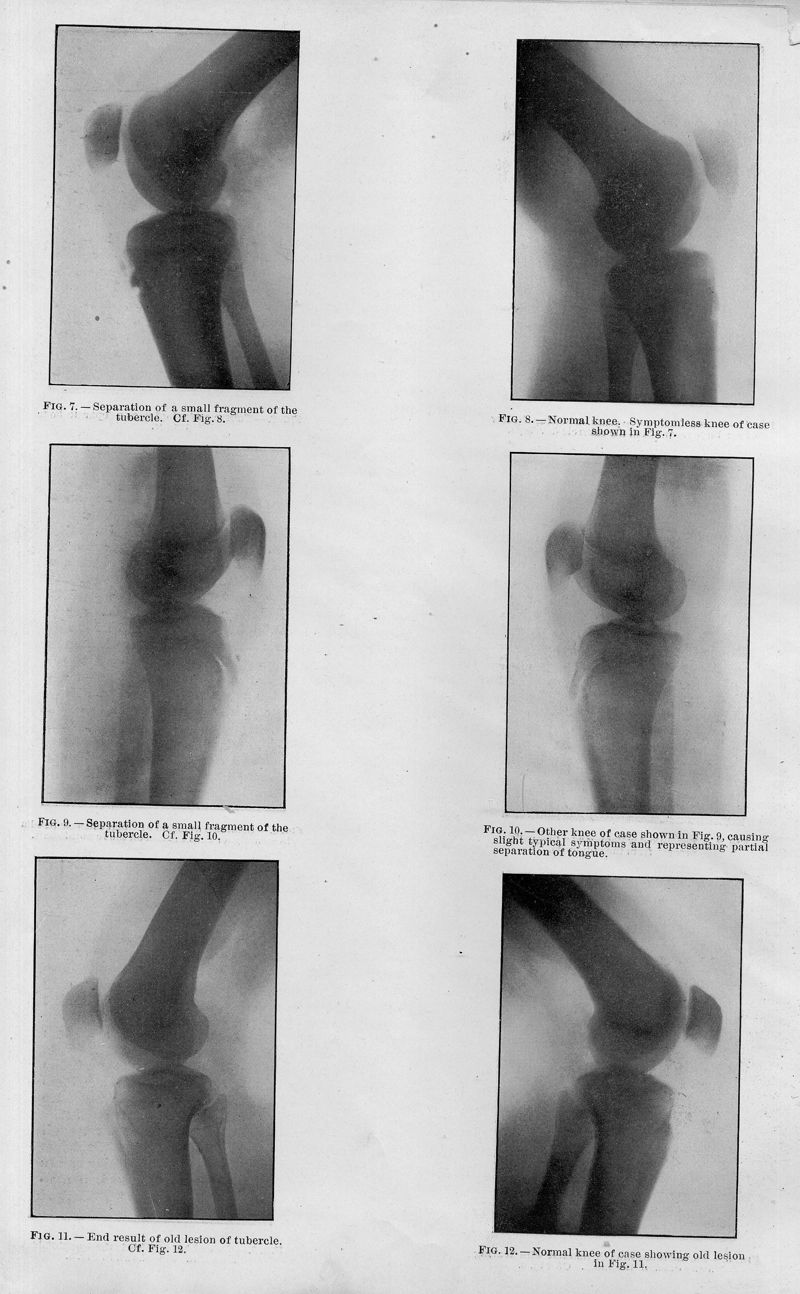

OSGOOD, Robert Bayley.

Lesions of the tibial tubercle occuring during adolescence

In : Boston Medical Journal, 1903, Vol. 148, pp. 114-7